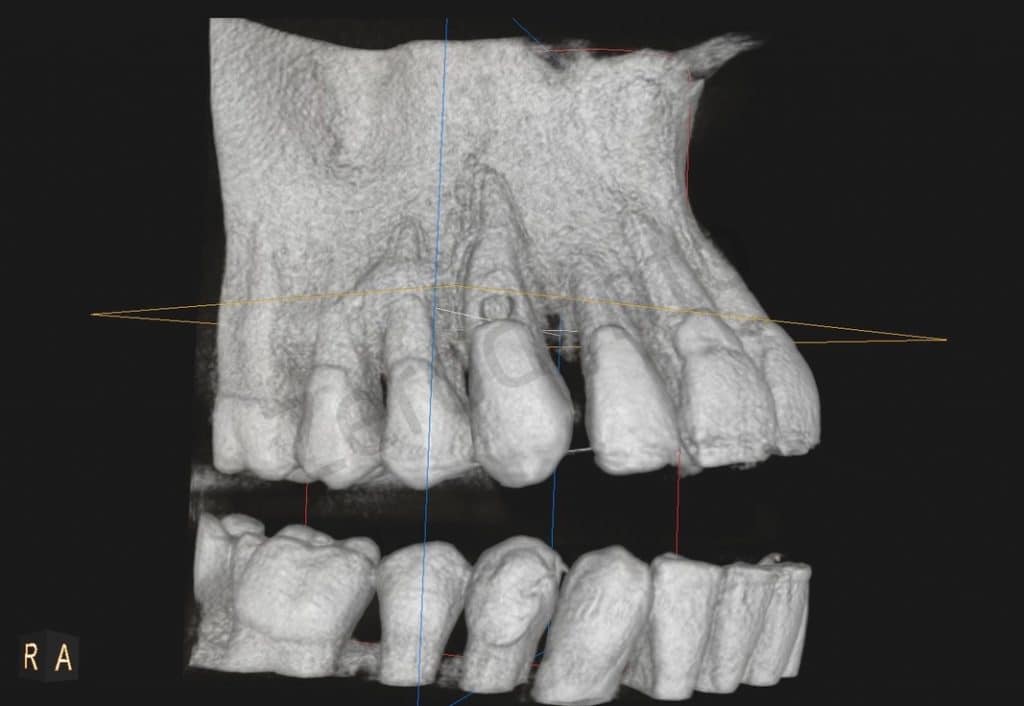

The cbct showed a lesion of about 4mm in diameter, which vestibularly affected the root #13, just below the junction.

CBCT